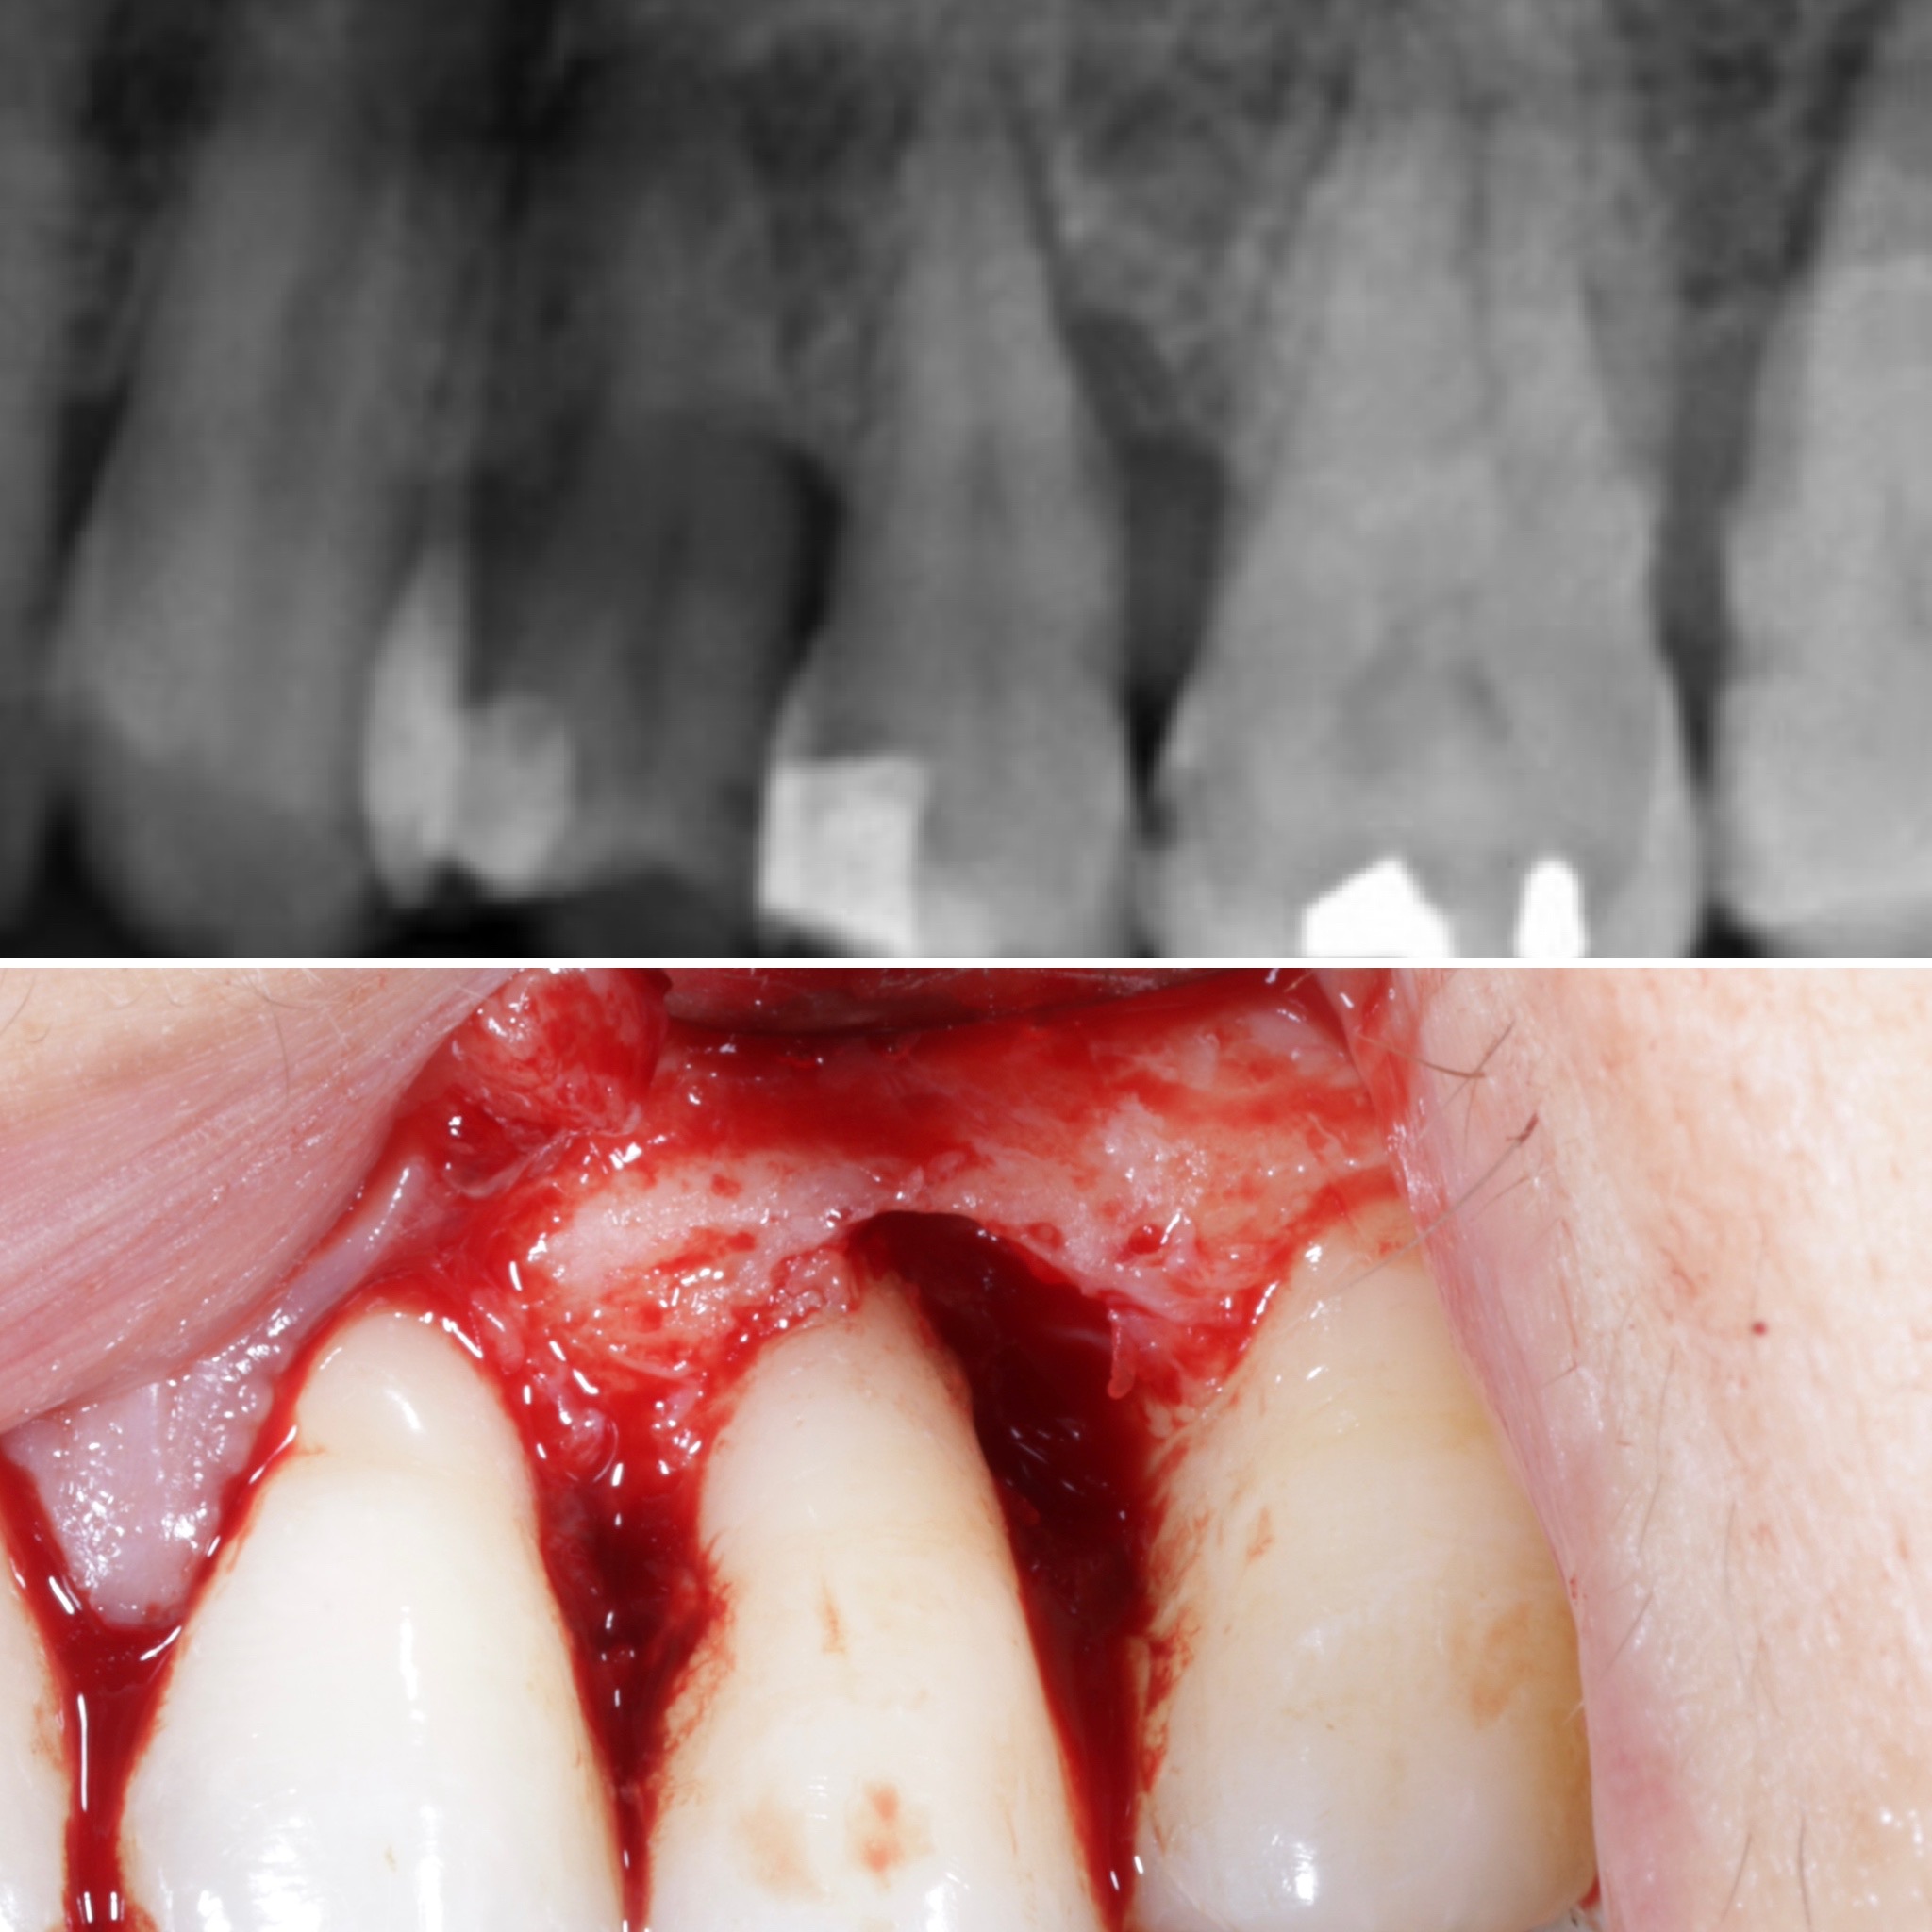

Durante una mañana, asistirás a una Cirugía Mucogingival de recubrimiento radicular de recesiones múltiples en IV y V sextante (36 a 43).

Gracias al uso del microscopio y a la proyección en tiempo real en pantalla, verás exactamente lo mismo que veo yo durante la cirugía, sin tener que estar

Podrás asistir a la planificación de casos y cirugía de injerto de tejido conectivo. Factores determinantes y elección de la técnica adecuada. Sumérgete en un protocolo predecible y técnicamente correcto para obtener resultados óptimos.

Aprende la planificación y técnica de la cirugía Mucogingival para el recubrimiento de recesiones y aumento de banda queratinizada en el sector anteroinferior

La formación comenzará con la presentación del caso clínico que se abordará durante el curso, seguida de una cirugía en directo, que permitirá observar paso a paso el procedimiento y la toma de decisiones clínicas. Durante la jornada se profundizará en los conceptos biológicos aplicados a